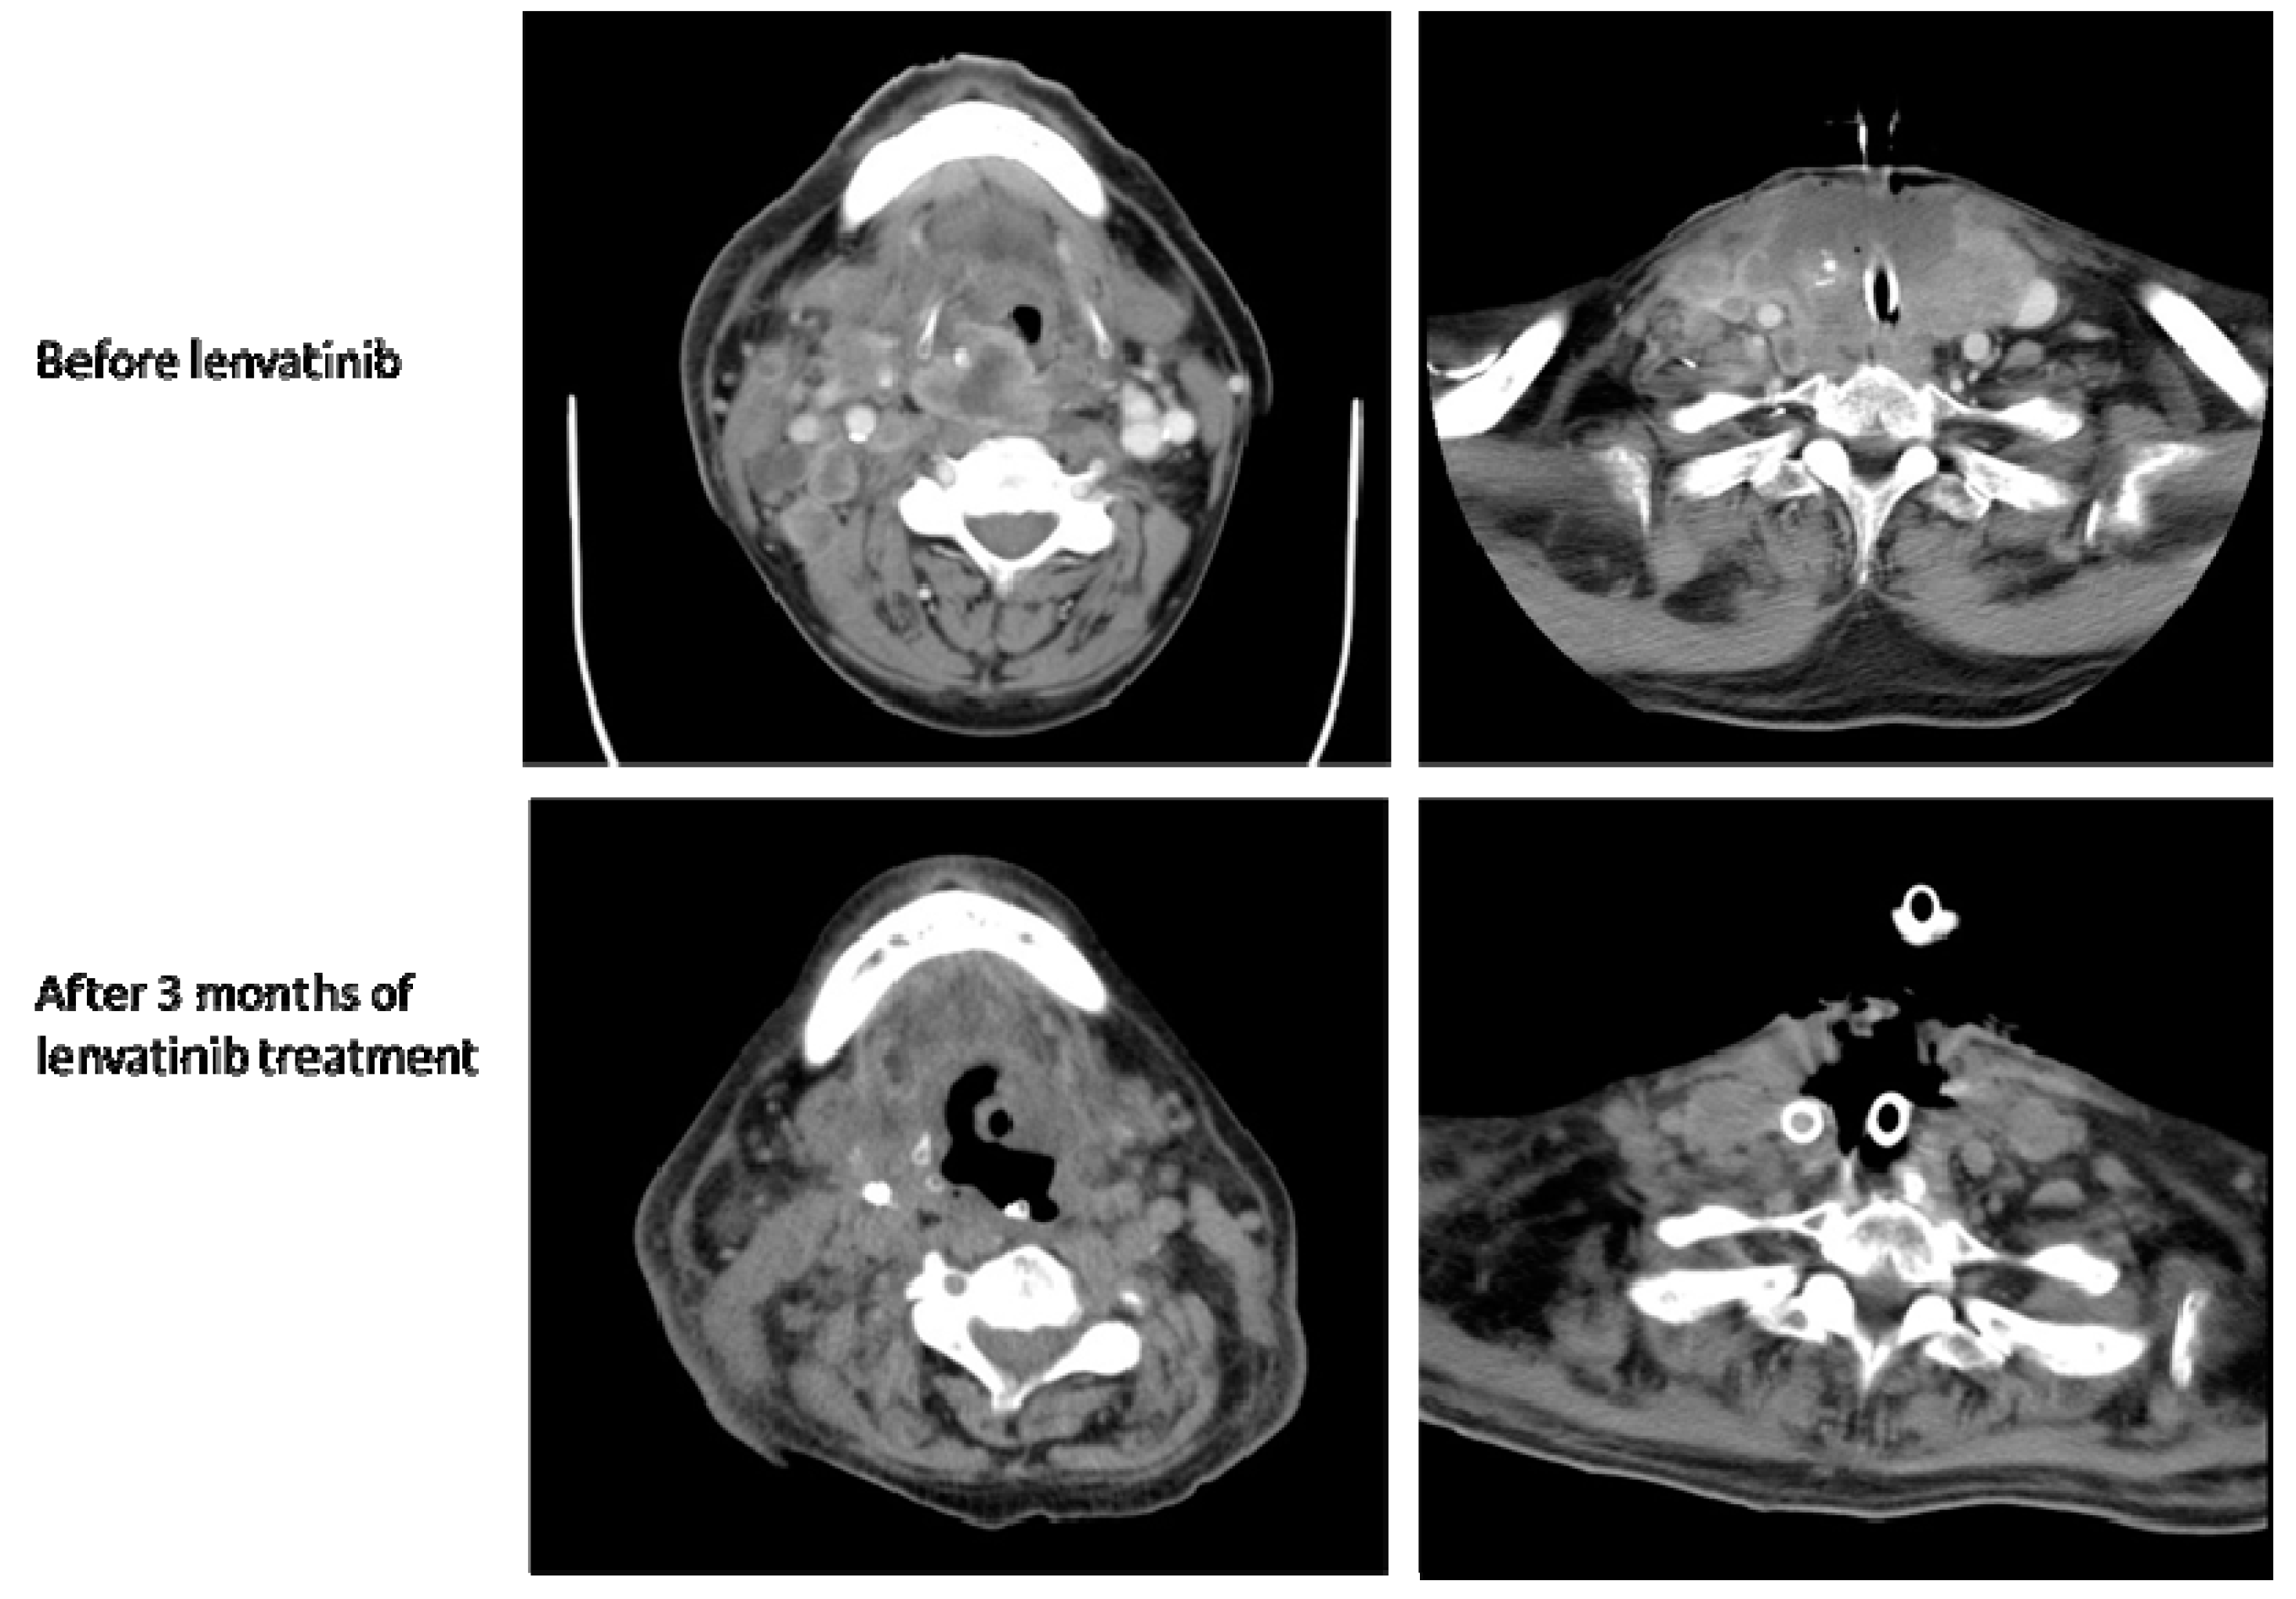

2.1. Case 1